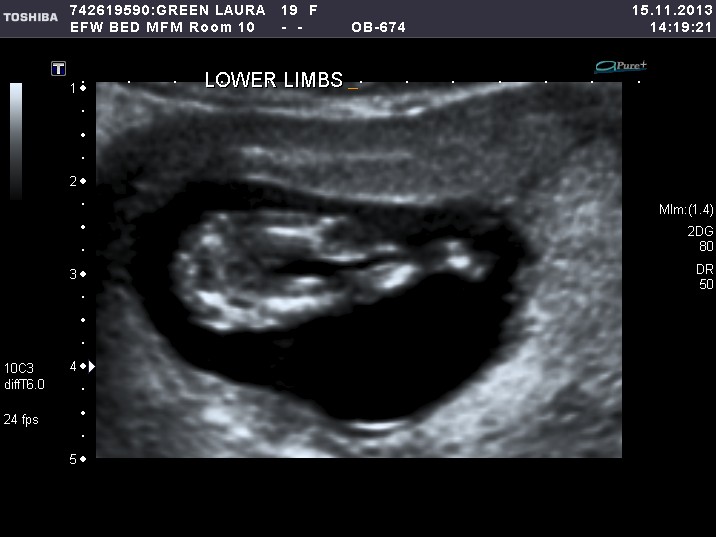

12 weeks 6 days nub photo boy or girl???

12 weeks 6 days nub photo boy or girl??? from www.genderdreaming.com

12 weeks 1 day ultrasound boy or girl?

12 weeks 1 day ultrasound boy or girl? from genderdreaming.com